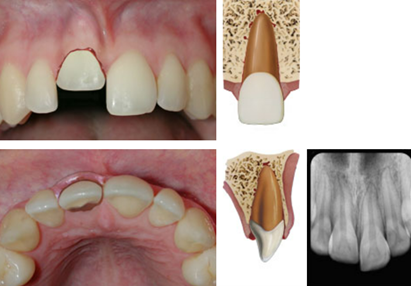

dx lateral luxation

A

Displaced usually in palatal/lingual or labial direction

High metallic/ankylotic sound

Usually mobile

Sensibility tests will likely give a lack of response except for teeth with minor displacements.

* The test is important in assessing risk of healing complications. A positive result at the initial examination indicates a reduced risk of future pulp necrosis.

Occlusal, PA and 2 eccentric exposures from diff horizontal angulations

* Widened PA ligament space